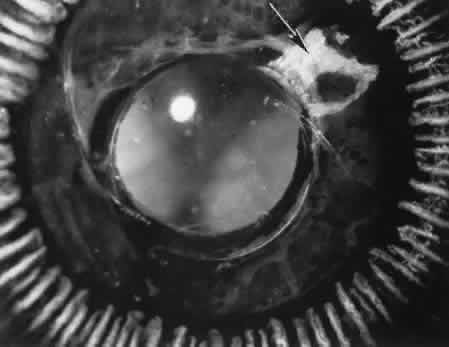

Iris or lens capsular incarceration into the wound and extending to the conjunctival space (Figs. 32 and 33) may act as a wick through which aqueous can escape, causing a flat anterior chamber. Histologically, iris, which is frequently recognized only by the presence of melanocytes, is seen in the limbal scar, in the limbal episclera, or in both areas.

Fig. 32. A case of retinal detachment. A. In this case, the iris has become incarcerated into a limbal wound. A series of events leads to total retinal detachment (morning glory detachment). The presence of multiple areas of macrocystic degeneration of the detached retina indicates that the situation is chronic and probably not repairable. B. The histologic section of this case indicates the extent of iris incarceration and the fragility of the wound. (Hematoxylin-eosin stain; × 40.)

Fig. 33. A case of iris prolapse through a limbal wound. A. A large black mass has appeared at the limbus of a patient with a history of cataract extraction. There may or may not be a history of trauma or Valsalva maneuver. The differential diagnosis at first glance would certainly include primary conjunctival malignant melanoma or extraocular extension of a primary uveal malignant melanoma. A major differential observation from iris prolapse is the character and degree of alteration of the iris tissue remaining within the eye. B. By histologic section no cellular mass is present either in the episcleral or uveal tissue. The remaining iris is stretched and adherent to the posterior corneal surface. (Hematoxylin-eosin stain; × 40.)